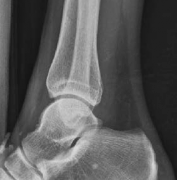

Tibial shaft fractures extending into the distal metaphysis and the tibial plafond represent a formidable challenge in orthopedic trauma. Historically, these complex injury patterns—often classified as AO/OTA 43-B or C, or 42 with distal extension—were managed primarily with plate osteosynthesis due to concerns regarding articular congruity and the inability of early generation intramedullary nails to secure short distal segments. However, the evolution of intramedullary nailing systems, featuring multi-planar distal locking options and advanced insertion trajectories, has revolutionized the management of these fractures.

The epidemiology of these injuries demonstrates a bimodal distribution. High-energy trauma, such as motor vehicle collisions and falls from height, typically afflicts younger patients and presents with significant soft tissue compromise, comminution, and complex articular involvement. Conversely, low-energy torsional mechanisms are more frequently observed in the elderly population, often resulting in spiral fracture patterns that propagate into the joint.